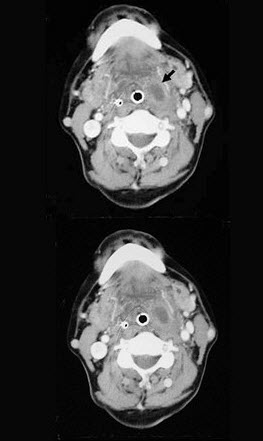

患者,男性,23岁,发热头痛3天,伴咽旁和颈部剧痛,吞咽困难,吐字不清,查体:扁桃体及咽侧壁突向咽腔,但无明显充血,CT检查结果如下图:患者最可能的诊断为()。

• A、咽旁脓肿

• B、扁桃体周脓肿(前上型)

• C、扁桃体周脓肿(后上型)

• D、咽后脓肿

• E、以上都不是

正确答案:A